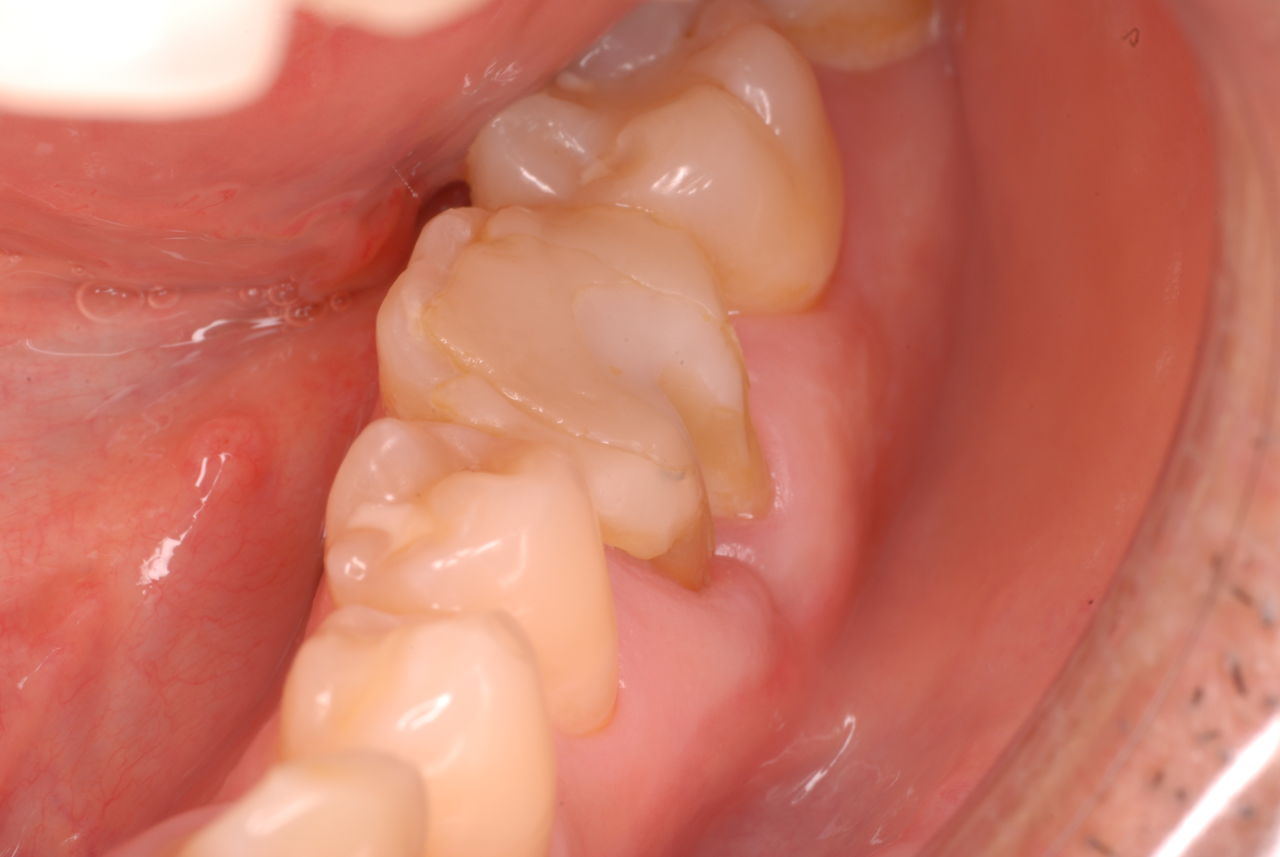

他の都心の矯正歯科で治療中で、ほぼ終了近くの方でした。歯並びで言えば上下の歯が突出していて唇が閉じにくいというのをなんとかしたい。そして歯を抜かないで出来るところを探して都心の矯正歯科への通院となりました。ところが本人曰くよく噛めないというのです。

相談しても“問題無い”の説明だけだそうです。調べたところ歯周病は進行しているし、奥歯の大きい歯2本ずつ計4本はしっかり噛んでいないのです。よく噛めないというのはそのことのようでした。これを矯正的に元に戻すことはできない訳ではありませんが、時間と手間がかかるのは間違いないことです。